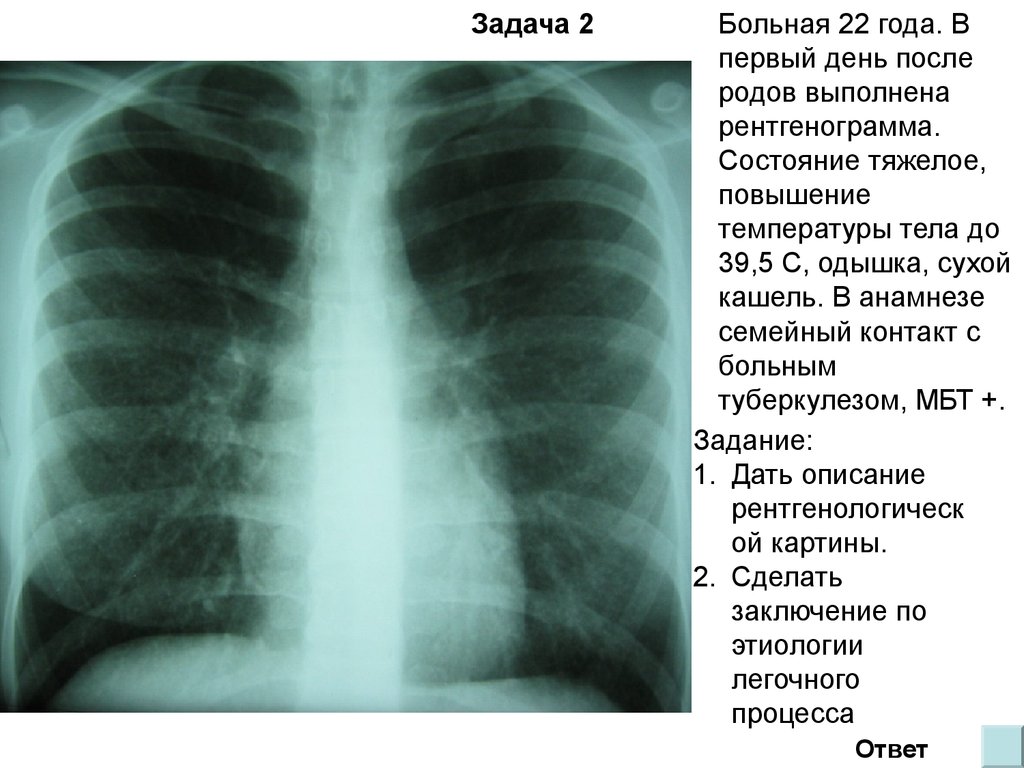

Симптомы и признаки туберкулеза: как распознать заболевание

Раздел: Визуальные уроки